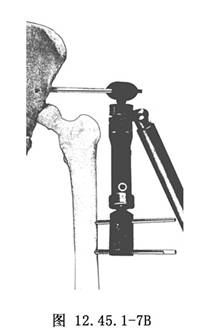

7.依據模板,擰入股骨的半徑針。擰入股骨半徑針時應將模板向前屈曲15°(相對於股骨軸線),爲了得到最大的穩定性,應選用模板上的第1和第5孔(圖12.45.1-7A)。全部半徑針擰入後,取掉模板和導針,將外固定架固定到上述半徑針上,擰緊固定螺栓,最後用扭矩扳手鎖緊萬向軸的凸輪(圖12.45.1-7B)。